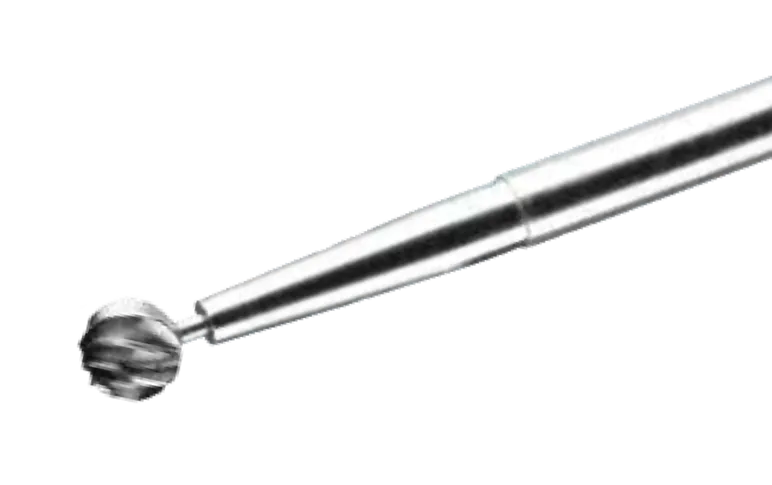

Fresas Transnasales

Las Fresas para la Base Craneal por Cirugía Transnasal son la última innovación para los enfoques endoscópicos...